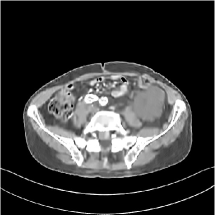

III.C. Low-dose Experiments with Mayo Clinic Data

First, we study transform training based on Mayo Clinic data. As shown in Fig. 6, seven slices obtained at regular dose from three patients are used for transform learning. The number of pixels . Similar to the phantom experiments, overlapping patches are extracted with a patch stride. The number of overall training patches is about . We set for ST, , , for MARS2, , , , , for MARS3, , , , , , , , , for MARS5, , , , , , , , , , , , , for MARS7. The iteration number in Algorithm 1. Fig. 7 illustrates the learned transforms obtained with Mayo Clinic data. Different from the XCAT phantom case, these transforms up to MARS5 display more complex features and structures. The rich features of the MARS models better sparsify the training images over layers compared to the single-layer model (ST).

III.C.2. Simulation Framework, Reconstruction Results, and Comparisons

The synthesized low-dose clinical measurements are simulated from regular-dose images at a resolution of mm with a fan-beam CT geometry corresponding to a monoenergetic source at incident photon intensity . The sinograms are of size . The width of each detector column is mm, the source to detector distance is mm, and the source to rotation center distance is mm. We reconstruct images of size with the pixel size being mm mm.

We conducted experiments on one test slice used for parameter tuning (L067-slice 120) and four independent test slices (L109-slice 90, L192-slice90, L333-slice140, L506-slice 100) of the Mayo Clinic data. For PWLS-EP, we ran iterations using relaxed OS-LALM and set regularization parameter . We used the same as the phantom experiments for Algorithm 2. The process of selecting a general set of reconstruction parameters () for the Mayo Clinic test slices is identical to that for the XCAT phantom in Section III.B.2. The selected regularization parameter and the parameters that control the sparsity of the coefficient maps are for ST, , , , , for MARS2, , , , , , , for MARS3, , , , , , , , , , , for MARS5, and , , , , , , , , , , , , , , for MARS7, respectively.

Figs. 8, 9, 10, and 11 show the reconstructions of the four independent slices using the FBP, PWLS-EP, PWLS-ST, PWLS-MARS2, PWLS-MARS3, PWLS-MARS5, and PWLS-MARS7 schemes, respectively. Additional Mayo Clinic experimental results of the parameter tuning case (Fig. 15) are shown in the supplementary document. Table 1 lists the RMSE and SSIM values of reconstructions of the four independent test slices, with the best values bolded. Generally, the five and seven layer models provided the best RMSE and SSIM values. They outperform the single-layer model by HU in RMSE on average. However, the MARS5 and MARS7 models perform similarly. In order to strengthen the benefits of the multi-layer model, Table 2 lists the RMSE of the reconstructions in four different ROIs (shown in the reference of Fig. 11) with seven methods for slice 100 of patient L506. By observing the reconstructed images, we see that although the ST model achieves a cleaner reconstruction result than FBP and PWLS-EP, it still sacrifices some sharpness of the central region and suffers from loss of details. The deeper models have a somewhat more positive effect in terms of maintaining subtle features, which is clearly more essential to clinical diagnosis. Furthermore, as we will discuss later, after considerable parameter tuning, we found that the information contained in residual maps is gradually decreased with the number of layers, eventually vanishing at some layer, which suggests that very deep unsupervised models might not offer significantly better image quality.